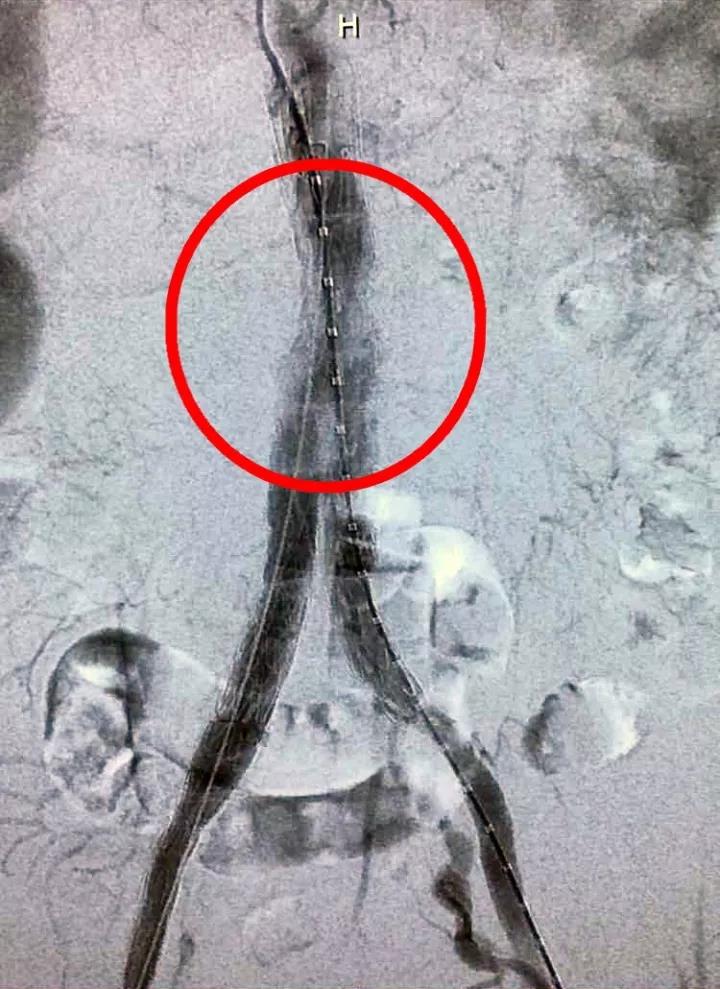

12月6日,患者被送入介入手術(shù)室,醫(yī)護(hù)人員同時(shí)以最快速度做好術(shù)前準(zhǔn)備。介入室中,手術(shù)團(tuán)隊(duì)根據(jù)DSA造影再次明確診斷及病變的手術(shù)指征,迅速對(duì)瘤體做出評(píng)估與測(cè)量,討論并確定了腹主動(dòng)脈瘤覆膜支架植入腔內(nèi)隔絕術(shù)的詳細(xì)手術(shù)方案。手術(shù)團(tuán)隊(duì)經(jīng)患者大腿股動(dòng)脈植入覆膜支架,將動(dòng)脈瘤腔隔絕后重建新的腹主動(dòng)脈腔血流通道。原動(dòng)脈瘤腔因無(wú)血流沖擊,瘤壁壓力得到解除,從而避免了瘤體的破裂。

經(jīng)三個(gè)多小時(shí)的多科室密切配合,患者體內(nèi)的腹主動(dòng)脈瘤被完全隔絕,這顆“人體定時(shí)炸彈”正式被“拆除”。目前,患者身體恢復(fù)良好,已于昨日出院。

手術(shù)后